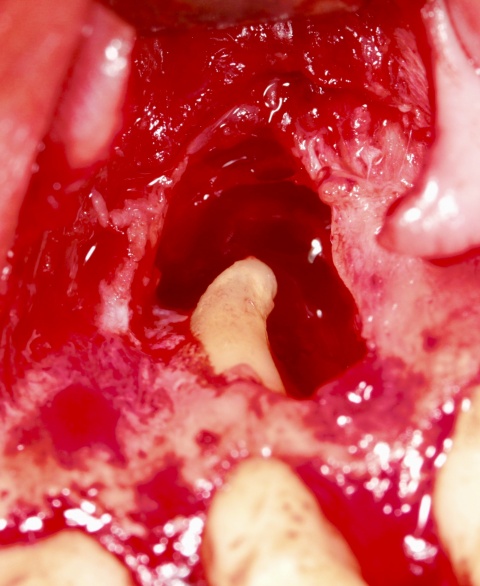

Nach eingehender Aufklärung des Patienten, entschieden wir uns für die Obturation des Wurzelkanals und der Via falsa sowie zur simultanen chirurgischen Entfernung der Wurzelspitze. Ziel war es auch, den nicht mechanisch und chemisch aufbereiteten Wurzelkanalanteil zuverlässig zu entfernen.

Nach Präparation eines Mukoperiostlappens und Darstellung der Wurzel wurde die apikal überpresste Guttapercha sichtbar. Nach Abtrennung der Wurzelspitze erfolgte die sonoabrasive retrograde Präparation mit gebogenen Aufsätzen der Firma Komet Dental (Gebr.Brasseler GmbH, Lemgo) und der retrograde Verschluss mit Biodentine™ (Septodont, Niederkassel). Die während des Eingriffs diagnostizierte Wurzelkaries wurde konservierend versorgt. Beim abschließenden Nahtverschluss mit 6/0 Optilene (Braun Surgical, Rubi) kamen vertikale Rückstichnähte zum Erhalt der Papillen, sowie Einzelknopfnähten im Bereich der Entlastungsschnitte zum Einsatz. Das zehn Monate später angefertigte Kontrollröntgenbild zeigt die vollständige Ausheilung der Resektionshöhle.